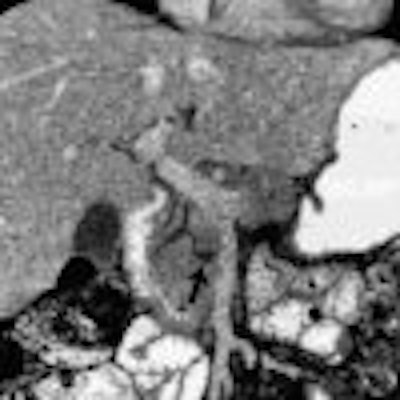

Chapter 7 -- The Pancreas

Located in the anterior pararenal space of the retroperitoneum, the pancreas occupies an anatomic location that is relatively accessible by clinical examination. The combined use of CT, MR, US, ERCP, and EUS has revolutionized pancreatic evaluation.

These complementary imaging modalities provide key information that guides clinical management for a diverse array of pancreatic diseases. Earlier diagnosis of pancreatitis and pancreatic ductal adenocarcinoma can lead to an improved clinical outcome.

In this chapter the clinical and imaging features of a variety of pancreatic diseases, including neoplasms, inflammatory conditions, and a host of other pancreatic conditions, are discussed.